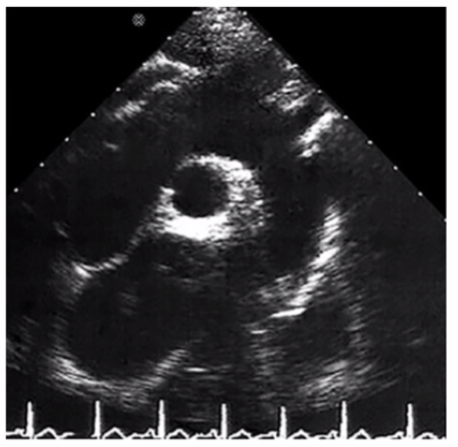

Identify the right pulmonary artery.

Using your mouse, place the cursor on the appropriate region of the image and then left click the mouse button to indicate your selection.